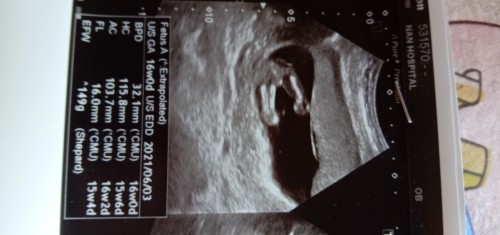

รูปนี้ได้ลูกสาวหรือลูกชายค่ะช่วยบอกหน่อยค่ะดูไม่เป็นค่ะ

อยากทราบมากค่ะว่าหญิงหรือชาย

น่าจะชายนะคะแต่ให้แน่ใจซาว์ดอีกรอบดีกว่าคะ

มัน50/50ค่ะแม่ รอซาวอีกรอบนะคะ